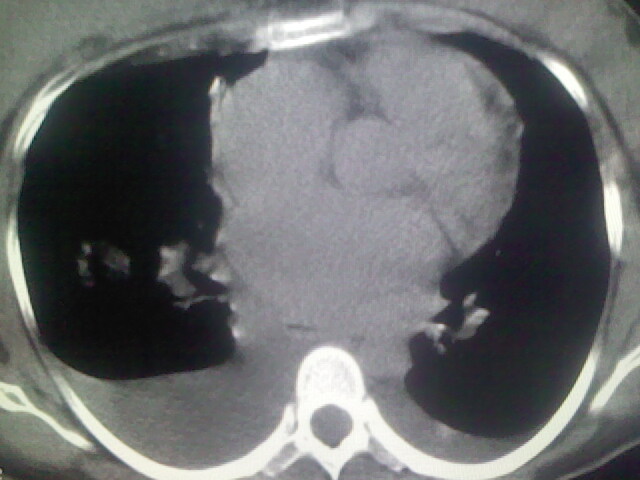

女,24,剖腹产后,突觉胸痛,干咳,不能平卧

做个增强的 ct吧 pte(肺血栓栓塞)不能除外啊 在结合心电图 看看v1-v4导连的t波及st段改变。

患者允许的情况下建议进行心脏超声检查

急性心衰可能,肺梗塞??我没看到病变的具体位置,楼上的给讲讲啊

考虑肺梗塞 双侧胸腔积液 心影增大 建议进一步检查吧

双肺水肿,双侧胸腔积液,肺梗死不能排除